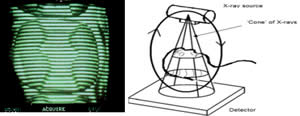

Introducción.- En oclusión, existen varios campos de aplicación básica para la digitalización. Hablamos, preferentemente, de la digitali- zación tridimensional. Recordemos que esta palabra es sinónimo de medición y –como tal- auxilio en esta rama odontológica tan necesitada de precisión. La digitalización tridimensional consistirá en el registro de la posición espacial, de un finito número de puntos, determinando sus coordenadas -x,y,z-. A menor distancia entre cada punto se conseguirá como resultado un objeto virtual con mayor detalle, coincidente con el real. Con cada triada se podrá formar una superficie, que continuada con la generada por el resto de la malla de puntos, completarán la forma del objeto. Este es el origen de donde partimos para establecer el concepto básico de las revolucionarias aplicaciones 3D. Se parte así del denominado escaneado tridimensional: Escaneado Superficial de un objeto real -> “Nube de Puntos” -> “Malla de Alambre” -> Superficie del Objeto Virtual. Con los modelos dentarios, impresiones o registros de oclusión, virtuales (en la pantalla del ordenador), realizaremos ahora, mediante un programa informático, la manipulación simulada, mediante computadora, para la realización del estudio y diseño de la oclusión. La Oclusión Computarizada (OC) –dentro de la más amplia Odontología Computarizada- comprende, hoy, fundamentalmente, tres fines: 1º)- El Estudio, Diagnóstico y Plan de Tratamiento Asistidos por Ordenador. 2º)- El Encerado Computarizado. (Por RP –Rapid Prototyping-, Prototipado Rápido, o por CAM –Computer Assisted or Aided Machining or Manufacturing-, Maquinado Asistido o Ayudado por Computador). 3º)- La Restauración y Confección de Prótesis Computarizada. (Por CAD-CAM, -Computer Assisted Design – Computer Assisted Manufacturing-, Diseño y Fabricación Asistidas por Computador). La Odontología Computarizada tiene entre sus numerosas secciones, ésta de oclusión, considerada primordial en el trabajo clínico habitual, desde la que nos relacionamos con la ortodoncia, cirugía implantológica, tecnología protésica y prostodoncia. Cada uno de los citados fines de la OC necesita partir de un escaneado tridimensional de los objetos a tratar: elementos del sistema dentario (arcadas) –de forma directa, en la misma boca del paciente-, o modelos dentales obtenidos por una impresión material de éstas y su posterior escaneado –o forma indirecta, fuera de la boca del paciente-. El escaneado se puede realizar con variados dispositivos, resultando procedimientos de distintos tipos y con diferentes características, clasificados simplificadamente como: A) Escaneado de contacto, háptico: B) Escaneado sin contacto: Tomando una imagen del objeto, marcado por líneas o cuadrículas luminosas proyectadas sobre su superficie, que se deforman con ella, analizándose luego digitalmente. El escaner se considera aquí un analizador trigonométrico del objeto, que registra su imagen, marcada mediante un rayado por luz –normalmente láser- (que permite, mediante software, obtener las coordenadas espaciales de multitud de puntos, que son agrupados en unidades de tres, constituyendo los vértices de una superficie triangular, que sumándose a las vecinas, llegarán a representar la envuelta completa del objeto y así su forma volumétrica o tridimensional). C) Combinado. Externo e Interno. Los escáneres suelen resultar, actualmente, poco económicos, y aunque van decreciendo en coste, están –para estas fechas- en un nivel que suele partir como mínimo de los 8.000 euros; siempre dependiendo del procedimiento de registro empleado, tamaño y precisión del escaneado. Existen: A) aparatos integrados en sistemas dentales, desarrollados específicamente para nuestro campo, de comprobada eficacia y de alto coste económico; B) dispositivos de uso general, aplicables a los propósitos de la odontología, de complicada adaptación pero de muy bajo coste relativo; C) múltiples posibilidades para la construcción de un escaner propio, casero y económico, que pueda, con suficiente experiencia, llegar a funcionar para uso profesional, gracias a la existencia de suficiente información de la tecnología empleada, ampliamente divulgada y de fácil desarrollo; útiles para fines diagnósticos. En oclusión necesitamos el 3D, pero también el 4D. Sumamos aquí a las tres coordenadas espaciales de cada punto del objeto, otra más, la cuarta dimensión: el tiempo. Dado que un objeto móvil, lo es por la temporalidad de sus posiciones en el espacio. Así se registrarán y analizarán digitalmente los movimientos mandibulares para conseguir la articulación y reproducción de la función masticatoria. Para esto se han aplicado determinados registros, mediante sensores de posición o por receptores de actividad muscular, como los electromiógrafos, o el más específico articulador virtual, del que se encuentran diferentes productos de software, englobados –como complemento necesario- en los programas que acompañan a los distintos sistemas de cad-cam dental. Desde el escaneado, o transformación u obtención del objeto real en cuerpo 3D, numérico, adquirido para ser estudiado y manipulado de forma digital, virtual, en el computador, continuamos con otras vías, ahora posibles, de enorme potencial, desde el estudio y planificación a la fabricación protésica. Así van a ser expuestas a continuación: A) La planificación; B) el encerado; y C) la fabricación. A) -Estudio, Diagnóstico y Plan de Tratamiento Asistidos por Ordenador. La planificación de la rehabilitación oclusal, puede iniciarse: A-1) Por Registro Estático Morfológico Computarizado, del aparato estomatognático y sistema dentario. Que puede realizarse: I) A partir de Escaneado Extraoral. I-a) Escaneado Volumétrico (CT–tomografía computarizada-) (O mejor, CBCT –tomografía computarizada de haz cónico-, de menor radiación y coste, con aparatos diseñados específicamente para uso dento-máxilo-facial ). I-b) Escaneado Superficial –de los modelos de estudio- y Registros Oclusales-. II) A partir de Escaneado Intraoral. II-a) Escaneado Volumétrico (CT local, o CBCT local, que se están desarrollando para aplicación retroalveolar). II-b) Escaneado Superficial –de las caras oclusales del sistema dentario-. A-2) Por Registro (Estático Morfológico Computarizado) de Huellas de Oclusión (o Registros Oclusales), para análisis de contactos intermaxilares, estáticos -y menos o indirectamente los movimientos mandibulares-. Mediante escaneado superficial de registros, sus modelos 3D, y combinación o no, con el Papel de Articular Electrónico (T-Scan). A-3) Por Registro Dinámico Funcional (fisiológico) Computarizado: I) Registro Computarizado (Integrado) de los Movimientos Mandibulares –electropantográfico o cinematográfico-. Por sensores o marcadores de posición. II) Registro Computarizado (Integrado) de la Función Muscular –electromiográfico-. A-4) Por Integración Informática de varios de los Registros citados. B) -Encerado Computarizado. Es el modelado o diseño virtual en la pantalla del ordenador y su realización en material de patronaje (como la cera u otro de similar; económico, modificable, transformable y rápido), que puede realizarse por: B-1) Por RP –prototipado aditivo- o B-2) por CAM –maquinado sustractivo-. Como pensamos en el concepto clásico, la realización de un encerado diagnóstico es clave para una rehabilitación oclusal correcta. Además el encerado servirá para la confección de: a) una posible férula radiológica y quirúrgica, b) una referencia para el tallado, la prótesis o rehabilitación temporal y el patrón para la definitiva. Se llevará a cabo, en dos etapas: 1ª) Etapa de creación del patrón. Elaboración virtual en la pantalla del ordenador. Necesitando el software apropiado, CAD. 2ª) Etapa de confección. Elaboración Real, mediante RP o CAM. 1ª) La etapa de creación virtual del patrón en la pantalla del ordenador, mediante un programa informático de diseño y manejo de objetos tridimensionales, (siempre partiendo de un registro previo, como el escaneado de los modelos), puede facilitarse con varias herramientas para: -Elaboración Virtual por Adición. 2ª) La etapa de confección, o elaboración real, mediante RP o CAM. -Confección por RP (Rapid Prototyping) –Prototipado Rápido-, de adición o construcción capa a capa, añadiendo una sustancia que se endurece, aumentando su nivel en superficie. La elaboración real por adición, es posible en un variado –pero limitado- tipo de materiales. -Confección por CAM (Computer Aided Machining) –Maquinado o Tallado Asistido por Ordenador-, de eliminación de sustancia o esculpido en un bloque sólido. La elaboración real por sustracción, es posible en un numeroso -y casi ilimitado- tipo de materiales. Existen gran cantidad de dispositivos que consiguen la fabricación y consecución física de un encerado real, a partir de su elaboración virtual, desde un escaneado y su diseño computarizado. Todos los sistemas denominados de cad-cam dental, en general, aunque no estén espe- cialmente dispuestos para ello, pueden dedicarse a este propósito; simplemente colocando un material de patronaje, como la cera, en lugar del material con el que se constituirá la prótesis definitiva. Pero, existen –también- sistemas espe- cialmente configurados para el trabajo en material de diseño, normalmente: ceras, resinas o compuestos, es lo que se denomina prototipado rápido (rapid prototyping). En la industria general, la fabricación de cualquier objeto en serie, requiere de estos procedimientos en las primeras etapas de elaboración para su producción. La más económica y reducida Impresora 3D o Sistema de Prototipado Rápido, que puede confeccionarnos unos maxilares, a partir de la tomografía, o un encerado diagnóstico, según el software disponible. Su precio actual 45.000 Euros. C) -Restauración y Confección de Prótesis Computarizada. (Por CAD-CAM). Es el modelado o diseño virtual en la pantalla del ordenador y su realización en material definitivo (como porcelana, titanio, aleación preciosa, u otro similar); poco económico, difícilmente o no modificable, ni transformable y que requiere de un tiempo adecuado, mucho mayor que el requerido para la confección del patrón de material plástico. Esto puede realizarse por numerosos dispositivos. Existen gran variedad de sistemas para el diseño y confección de restauraciones y prótesis. Son los denominados gene- ralmente SISTEMAS DE CAD-CAM DEN- TAL (Dental Cad-Cam System): (Entre estos sistemas encontramos los que también pueden planificar el tratamiento restaurativo y realizar el encerado diagnóstico con diseño y confección de un patrón oclusal; como hemos referido antes). Históricamente estos sistemas comenzaron con la década de los setenta -en 1971, con el Holodontography-Altschuler System-, y con el Sopha System de Duret, progresando enormemente hasta comienzos de los noventa. Durante esos veinte años, se potenció su desarrollo con el siguiente hito histórico que los encumbró, en su segunda década, por la aparición de los principales impulsores del cad-cam clínico comercializable -Mörmann y Brandestini, en 1981-, denominado Sistema Cerec. También se establecieron los principios de estos dispositivos con el DCS Dental System, el CAP System, el Minnesota-Rekow System, el Nissan Cad/Cam System, Automill y Microdenta System. El culmen del progreso se alcanzó a mediados de los noventa, con sistemas ampliamente comercializados y evolucionados hasta hoy: Procera, DCS Dental, o Cicero. En los siguientes diez años, se continuó perfeccionando los sistemas citados; hubo algunos sistemas no comerciales o de escasa difusión, o distribuidos moderadamente; repre- sentando un período hasta el 2000, con una pequeña depresión, en los años medios, por el declive en la extensión de estos productos, en relación al extraordinario futuro que se les auguraba, motivada por el alto coste de los equipos y las limitaciones en su potencia digital, en el que –aún y así- aparecieron sistemas como: Belledent, Cadim, Dentscan, CCD System, Cynovad, Digident-Girrbach, Decim y Etkon. La segunda revolución para la odontología por cad-cam se produjo con el comienzo del siglo. Ampliándose enormemente la cantidad de sistemas y alentándose una explosión del trabajo digital en odontología, con: Cercon-Degussa, Lava-3M-Espe, Cad-Esthetics System-Ivoclar, DDS, GC-Dental, Everest-Kavo y Bego. En estos momentos el futuro de la odontología se encuentra inexorablemente unido a estos aparatos. Para el clínico o el laboratorio dental es hoy imprescindible contar con ellos. Siguen nuevas apariciones, como el sistema Hint-Els, o el Evolution-4D, similar al Cerec, que fue el pionero, pero que todavía, a la fecha, se mantiene como el más versátil, modulable y práctico, con progresos como el facilitado trabajo de diseño tridimensional o el nuevo escaneado extraoral independiente. Los sistemas de cad-cam, están integrados por: un escaner que digitaliza el objeto dental, un ordenador con el software adecuado para el diseño virtual, y una máquina de tallado para la fabricación del objeto diseñado en un material determinado. Una relación actualizada, de gran número de los sistemas existentes se encuentra en “Aktuelle CAD/CAM Systeme”, en http://www.tu-dresden.de/medprothetik/computerzahn/CAD-CAM-Systeme.htm Factores clave en la Oclusión Computarizada-. La digitalización del estudio, diagnóstico y tratamiento de la oclusión, como la construcción o restauración de un sistema dentario óptimo para la correcta función masticatoria del aparato estomatognático, pretende facilitar y generalizar la excelencia en el trabajo clínico. Es una aplicación de preferencia informática porque pueden manejarse gran cantidad de datos, mediciones, relaciones geométricas, unidas a la tridimensionalidad y la movilidad de sus elementos, de una forma racional, lógica y científicamente fundamentada, aún partiendo de concepciones filosóficas o criterios sujetos a distintas escuelas de oclusodoncia. La digitalización de la oclusión pude llevar- nos a despejar supuestos sin evidencia científica, de la que adolece sectorialmente nuestro arte. Tenemos suficientes fórmulas, reglas y relaciones numéricas, aportadas por numerosos autores, que tienen que se recopiladas y que pueden así ser aplicadas. Yá que la digitalización recoge todos los datos métricos y posicionales (coordenadas de cada punto, con su x,y,z), del sistema dentario, se pueden establecer fórmulas matemáticas para que -siendo la z la determinante de la altura de un punto en el espacio-: una z máxima, de una pieza mandibular, esté más o menos próxima a una z mínima de una pieza maxilar; que un punto (de cúspide) -con una determinada x,y- maxilar, coincida con otro –con la misma x,y- mandibular, pero con distintas aunque casi idénticas z, dándose el contacto oclusal. Y de esta forma, con sucesivas relaciones (matemáticas) se construiría una oclusión tendente a la excelencia; matemáticamente desarrollada. Así podría confeccionarse, automáticamente, una oclusión geométrica, dando, por ejemplo, solamente: la posición base de cada pieza, la x,y de las cúspides de una hemiarcada, y la altura de su plano oclusal, y automáticamente se generarían las cúspides agonistas y antagonistas, y la morfología dental completa de ambas arcadas. Se tendrían que añadir los datos correspondientes a los dientes anteriores, a las ATMs y las fórmulas de relación de las pendientes. Distintos autores han desarrollado relaciones métricas en oclusión. Algunos han simplificado el proceso, como partida, para ir añadiendo variantes; así, pueden usarse valores standard, normales, del ángulo cuspídeo para fabricar la morfología oclusal en CAD/CAM, -cuando la creación del esquema oclusal es de novo-, según Hobo y Takayama; y el uso de varios valores fijos de partida, universalmente aceptados, en lugar de la medida directa de la pendiente condilar es, según los mismos autores, muy importante en el desarrollo extenso de los sistemas de CAD/CAM. Así, el procedimiento de «twin-stage» propuesto por estos autores, en su libro “Oral Rehabilitation”, proporciona una solución en la producción de una oclusión dinámica tridimensional para el CAD/CAM. Otra técnica, consiste en el encerado virtual, mediante un modelado CAM, siguiendo las etapas de Shillimburg, o Kuwata, elaborando paso a paso la morfología oclusal, orientada a su enfrentamiento con el antagonista, encaminando los volúmenes cuspídeos como en el encerado progresivo clásico, gota a gota. Se realizaría su construcción virtual en la pantalla del ordenador, pudiendo estar facilitada su manipulación, mediante “espátulas de encerado virtual”, utilizando los digitalizadores de brazo articulado, con los que se pueden disponer los volúmenes necesarios, en la posición espacial que se desee. No obstante, el modelado dental se puede realizar siempre, aunque sea a través del clásico ratón del ordenador, de forma virtual, con la imagen tridimensional en la pantalla, utilizando diferentes procedimientos, con el software adecuado: A) Automático, a partir de las reglas dentométricas, odontométricas y cefalométricas, relacionadas con la gnatología, tomando previamente los valores claves necesarios del paciente. B) Mediante diseño de la anatomía con trazado de los perfiles, líneas y curvas, que van a definir las superficies dentales. Trabajando bidimensionalmente, en base a cortes de la estructura a construir, que manipulada variando sus dos dimensiones, va a corresponderse con la morfología dental tridimensional, al establecerse un área de influencia y cambio en los cortes vecinos, y así alterándose el volumen dental completo. Este era el procedimiento de variación anatómica utilizado, durante dos décadas con el Sistema Cerec (el Cerec 1, Cerec 2 y Cerec 3), hasta la llegada del Cerec 3D. C) Mediante copiado de la cara oclusal ideal, realizada previamente en cera u otro material real, del diente, su registro oclusal o su antagonista, en el concepto original del Sistema CEREC, de construcción oclusal mediante Correlación –copiando un encerado previo- o Función –correspondiendo automáticamente a la cara oclusal del antagonista-. D) Mediante selección de dientes, individuales o en grupo (incisivos, caninos, premolares, molares, arcadas, hemiarcadas, sistema dentario, maxilares o mandibulares), de entre un grupo de archivos de modelos dentales tridimensionales virtuales, como una librería de objetos 3D. Como en la selección de las tablillas de dientes para la confección de las prótesis completas. Escogiendo tamaño y forma. Colocando cada pieza o bloque en su lugar, con la disposición espacial y oclusal correspondiente. E) Mediante la misma selección, antes citada, seguida luego de una transformación, como estiramiento o estrechamiento, u otras variaciones morfológicas, con las herramientas de edición del programa informático, hasta conseguir la oclusión que se pretende. F) Mediante encerado virtual, de adición progresiva de volúmenes anatómicos, en el concepto clásico de encerado gota a gota, con la metódica de P. K. Thomas, para restauraciones parciales, o de Kuwata, para rehabilitaciones extensas. El método de encerado es el que nos permitirá la construcción de una oclusión individualizada. Pero la necesidad de utilización de un articulador es evidente. Es presumible que se desarrollen nuevos instrumentos para la perfección de la oclusión computarizada, semejantes a los articuladores mecánicos tradicionales. Serán los denominados articuladores virtuales, (VA –Virtual Articulator-), o simuladores digitales de la articulación oclusal, consistentes en un programa informático, capaz de relacionar los modelos virtuales, permitiendo movimientos similares a los naturales del paciente: es la aplicación de la tecnología de la realidad virtual a la oclusión (VR –Virtual Reality-). Esto es lo que nos permitirá pasar de la fórmula empleada generalmente para el modelado oclusal, que suele ser estática y referida a un registro de las superficies antagonistas, a un sistema experto que reproduzca la relación completa de ambas arcadas, las articulaciones, y su combinación con los movimientos masticatorios: realizando la dinámica mandibular. Hoy en la mayoría de los sistemas de cad-cam, los trabajos oclusales se realizan, extensamente, basados sólo en el enfrentamiento con el antagonista, sin tener en cuenta la movilidad mandibular, las guias condilares o anteriores. Es como si realizásemos un encerado oclusal sin tener en cuenta los determinantes anteriores y posteriores, y trabajásemos en un articulador, no ajustable, o simplemente en un Oclusor o Verticulator, sin giro de cierre ni desplazamientos horizontales.El articulador virtual, por software, para el diseño oclusal en la pantalla del ordenador, aún no es empleado de forma generalizada en estos sistemas, pero ya se encuentran como aplicaciones en algunos de ellos. Uno de los pioneros se utiliza en el sistema Cynovad. Aquí, directamente relacionado con la confección de un encerado oclusal. Otros dispositivos electrónicos y digitales, de registro por ordenador, que podrían combinarse con la construcción plástica de la oclusión, en cera u otro material, solo se están utilizando para diagnóstico, o como complementos a articuladores mecánicos sofisticados; así podemos encontrar programas como Rosy32 Robot System (Diagnostic Articulator), de registro dinámico, el VirtSet, de diagnóstico y predicción oclusal-ortodóntica, o el ArtiKulator-Software (ver ArtiDemo), de programación virtual de un articulador, con elección del equivalente mecánico real (Sam, Artex, Kavo,…). Entre éstos, el sistema más completo desarrollado, con escaneado de modelos y registros, y correspondencia con la dinámica mandibular, obtenida por un arco facial cinemático, con sensores de posición y movimiento, es el DentCAM.Para clasificar los instrumentos de oclusión, consideramos muy completa la clasificación de los articuladores mecánicos, desarrollada en The International Workshop Occlusion, de 1972, University of Michigan: 1) Clase I – Sujetadores simples de modelos. Subdivisión A (Con movimientos verticales; Corelator, Verticulator). Subdiv. B (Con articulación de bisagra sin desplazamientos horizontales; Centric Relator). Conclusiones (parciales para esta primera parte).- El articulador virtual podría establecerse a partir del escaneado de un articulador mecánico seleccionado, a partir de un modelo construido íntegramente por CAD de forma virtual, o –idealmente- a partir de un patrón anatómico, individual, a partir de la radiología tridimensional (como la Tomografía Computarizada). A estas estructuras se les sumarán los datos necesarios para la función: relación intermaxilar –estática- (oclusal) y relación cráneo-mandibular dinámica (pendiente condílea y Bennett), con ayuda también del registro de la actividad muscular (electromiografía). A la clasificación de los articuladores antes expuesta, le podemos añadir ahora el Tipo V, constituido por los Articuladores Virtuales, o instrumentos informáticos que pueden reproducir la oclusión dental en el ámbito de la realidad virtual, que se desarrollan como programas informáticos concretos, de muy variada composición en sus elementos de software, y distintos por los diferentes tipos de registros que necesitan para su efectiva y precisa actuación. Dentro de este V grupo, a su vez, podríamos –paralelamente a la clasificación de los articuladores mecánicos-, establecer tantas subclases como las de los tipos y subclases de aquellos. Así habría de clase I, como ocurre mayoritariamente en los sistemas de Cad-Cam dental actuales, cuando utilizamos modelos dentales 3D y registros estáticos de antagonistas. Es éste el cambio que se experimentará en los próximos años, en la Oclusión Computarizada: la utilización generalizada de Articuladores Virtuales de clase III y IV. Bibliografía Cooper BC. Parameters of an optimal physiological state of the masticatory system: the results of a survey of practitioners using computerized measurement devices. Cranio. 2004 Jul;22(3):220-33. Reiss B. Occlusal surface design with Cerec 3D. Int J Comput Dent. 2003 Oct;6(4):333-42 Petrie CS, Woolsey GD, Williams K. Comparison of recordings obtained with computerized axiography and mechanical pantography at 2 time intervals. J Prosthodont. 2003 Jun;12(2):102-10. Kojima T, Sohmura T, Nagao M, Wakabayashi K, Nakamura T, Takahashi J. A preliminary report on a computer-assisted dental cast analysis system used for the prosthodontic treatment. J Oral Rehabil. 2003 May;30(5):526-31 Bernhardt O, Kuppers N, Rosin M, Meyer G. Comparative tests of arbitrary and kinematic transverse horizontal axis recordings of mandibular movements. J Prosthet Dent. 2003 Feb;89(2):175-9 Tsai HH. A computerized analysis of dental arch morphology in early permanent dentition. ASDC J Dent Child. 2002 Sep-Dec;69(3):259-65, 234 Ferrario VF, Sforza C, Serrao G, Schmitz JH. Three-dimensional assessment of the reliability of a postural face-bow transfer. J Prosthet Dent. 2002 Feb;87(2):210-5. Kerstein RB. Current applications of computerized occlusal analysis in dental medicine. Gen Dent. 2001 Sep-Oct;49(5):521-30 Kerstein RB, Wilkerson DW. Locating the centric relation prematurity with a computerized occlusal analysis system. Compend Contin Educ Dent. 2001 Jun;22(6):525-8, 530, 532 passim; quiz 536. Sohmura T, Kojima T, Wakabayashi K, Takahashi J. Use of an ultrahigh-speed laser scanner for constructing three-dimensional shapes of dentition and occlusion. J Prosthet Dent. 2000 Sep;84(3):345-52. Kerstein RB. Computerized occlusal management of a fixed/detachable implant prosthesis. Pract Periodontics Aesthet Dent. 1999 Nov-Dec;11(9):1093-102 Tarantola GJ. A computerized model for teaching various methods of positioning the condyles to centric relation. Gen Dent. 1999 May-Jun;47(3):308-12 Gsellmann B, Schmid-Schwap M, Piehslinger E, Slavicek R. Lengths of condylar pathways measured with computerized axiography (CADIAX) and occlusal index in patients and volunteers. J Oral Rehabil. 1998 Feb;25(2):146-52 Tamaki K, Celar AG, Beyrer S, Aoki H. Reproduction of excursive tooth contact in an articulator with computerized axiography data. J Prosthet Dent. 1997 Oct;78(4):373-8 Garcia Cartagena A, Gonzalez Sequeros O, Garrido Garcia VC. Analysis of two methods for occlusal contact registration with the T-Scan system. J Oral Rehabil. 1997 Jun;24(6):426-32 Matsui Y, Ohno K, Michi K, Suzuki Y, Yamagata K. A computerized method for evaluating balance of occlusal load. J Oral Rehabil. 1996 Aug;23(8):530-5 Giddon DB, Sconzo R, Kinchen JA, Evans CA. Quantitative comparison of computerized discrete and animated profile preferences. Angle Orthod. 1996;66(6):441-8 Matsui Y, Neukam FW, Wichmann M, Ohno K. A computerized method for evaluating distribution of occlusal load on implant-supported fixed cantilever prostheses. Int J Oral Maxillofac Implants. 1996 Jan-Feb;11(1):67-72 Hayashi T, Saitoh A, Ishioka K, Miyakawa M. A computerized system for analyzing occlusal relations during mandibular movements. Int J Prosthodont. 1994 Mar-Apr;7(2):108-14 Maness WL. Computerized occlusal analysis. J Can Dent Assoc. 1993 Aug;59(8):701-2 Edwards CL, Richards MW, Billy EJ, Neilans LC. Using computerized cephalometrics to analyze the vertical dimension of occlusion. Int J Prosthodont. 1993 Jul-Aug;6(4):371-6 Giannazzo E, Leonardi R, Scivoli M, Rapisardi CB, Vassallo V. [Computerized parametrization in orthognathodontics] Boll Soc Ital Biol Sper. 1993 Jun;69(6):373-9 Harvey WL, Osborne JW, Hatch RA. A preliminary test of the replicability of a computerized occlusal analysis system. J Prosthet Dent. 1992 May;67(5):697-700 Boening KW, Walter MH. Computer-aided evaluation of occlusal load in complete dentures. J Prosthet Dent. 1992 Mar;67(3):339-44 Reza Moini M, Neff PA. Reproducibility of occlusal contacts utilizing a computerized instrument. Quintessence Int. 1991 May;22(5):357-60 Harvey WL, Hatch RA, Osborne JW. Computerized occlusal analysis: an evaluation of the sensors. J Prosthet Dent. 1991 Jan;65(1):89-92 Palano D, Molinari G, Salvo C. [Electromyography and computerized magnetic gnathokinesiography in the diagnosis and therapy of craniomandibular disorders] Minerva Stomatol. 1990 Dec;39(12):977-87

-B-2) Transfisivo, o volumétrico:

Radiológico, Resonomagnético o Ultrasónico,…

Realizándose un barrido del objeto en toda su profundidad, se registra la densidad y posición de cada punto, equivalente a un prisma macizo (voxel), más o menos denso, o hueco, que sumado a los restantes volúmenes contiguos, conformarán, mediante un análisis informatizado, el cuerpo tridimensional completo del objeto explorado, con su estructura interna y su superficie externa.